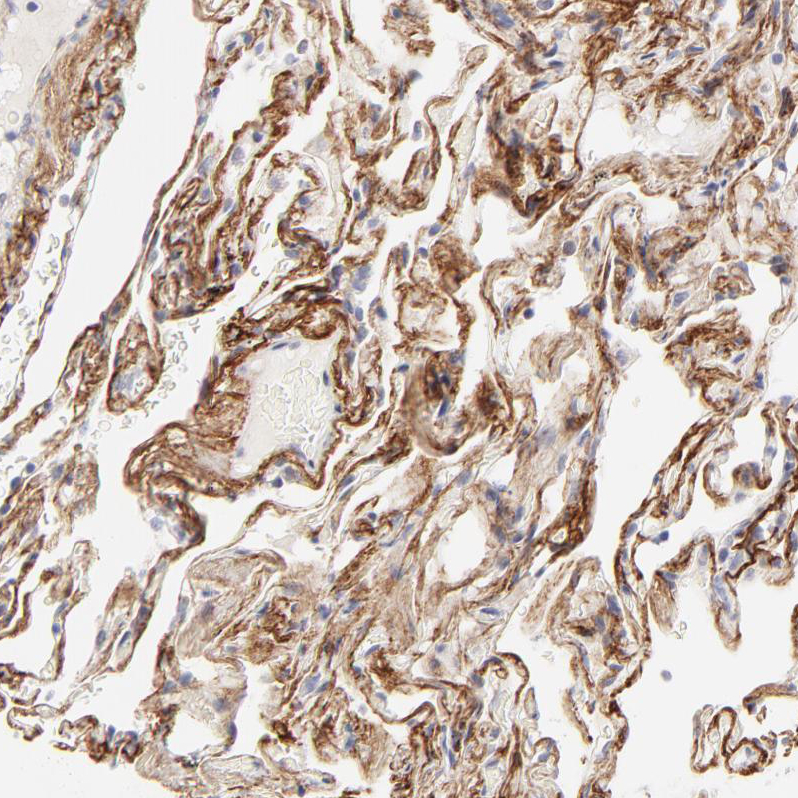

Immunohistochemical staining of human Lung shows moderate positivity in extracellular matrix in pneumocytes.